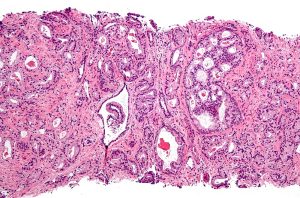

Eturauhassyöpä on pian helpompi estää

12.01.2014

10:45